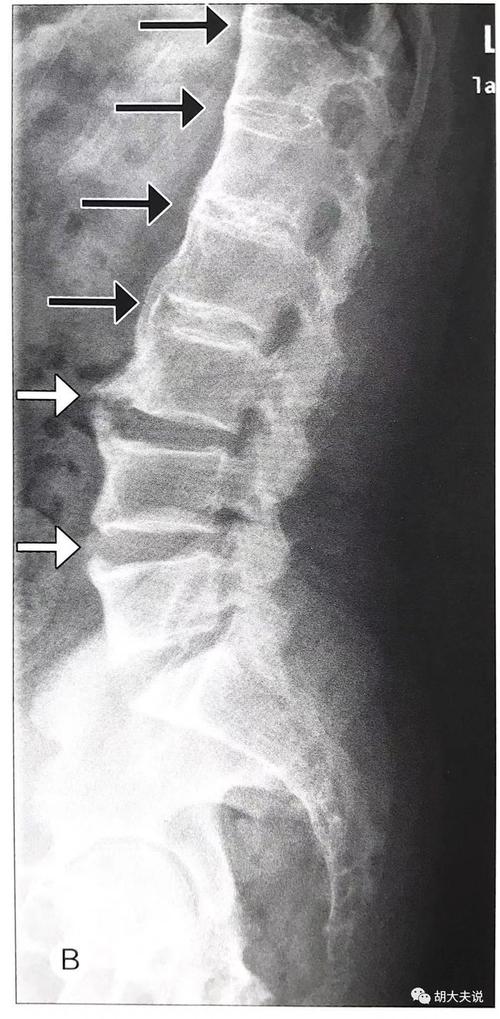

强直性脊柱炎骶髂关节ct分级和竹节样改变